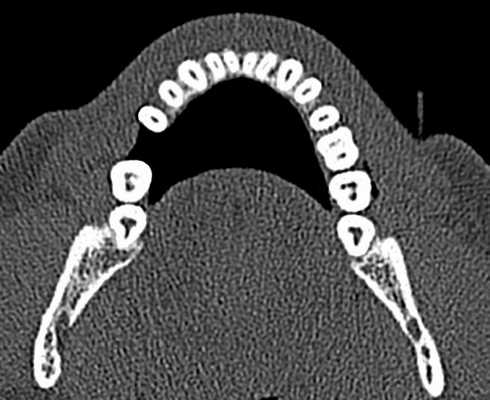

Сверхкомплектный моляр: обзор редкого случая

Сверхкомплектные зубы или гипердонтия - это стоматологическая аномалия, которая определяется как присутствие зуба или любой ткани зуба сверх набора 20 молочных и 32 постоянных зубов. Сверхкомплектные зубы могут возникать единично, группами, односторонне, двусторонне, они могут прорезываться или быть импактными на одной или обеих челюстях, как в молочном, так и в постоянном прикусе. Частота встречаемости в молочном прикусе варьирует от 0,1% до 3,8% и от 0,3% до 0,6%. В постоянном прикусе аномалия чаще встречается у мужчин, чем у женщин в соотношении 2:1. Однако данная диспропорция по полу не наблюдается в молочном прикусе. Также есть данные, что азиатская популяция более подвержена аномалии. Единичные сверхкомплектные зубы встречаются в 76-86% случаев, двойные в 12-23% и множественные - менее 1%. Множественная гиперодонтия редко встречается у людей без каких либо других сопутствующих заболеваний и синдромов. Обычно такая аномалия является частью системных расстройств, таких как расщелина губы и неба, клейдокраниальный синдром, синдром Гарднера, синдром Фабри-Андерсона, хондроэктодермальная дисплазия, синдром Эйлера-Данлоса и трихо-рино-фалангеальный синдром.

Сверхкомплектные зубы могут быть найдены практически в любой зоне зубной дуги. Локализация на верхней челюсти встречается гораздо чаще, чем на нижней, особенно в передней области (80%). Несколько реже сверхкомплектные зубы могут располагаться в дистомолярной зоне, нижних и верхних премоляров, в зоне верхних клыков и нижних резцов.

Наиболее ценным рентгенографическим исследованием является ОПГ с дополнительными прицельными снимками и снимками верхней и нижней челюсти в окклюзионной плоскости. Для четкой локализации непрорезавшегося зуба используют технику вертикального или горизонтального параллакса. Параллакс - это изменение обзора объекта на определенном фоне, основанное на перемещении обозревателя. Данная техника может быть осуществлена путем изготовления снимков одной зоны, но с разных углов двумя разными аппаратами. При использовании этого метода, как правило, точкой отсчета является корень примыкающего зуба. Вдобавок возможно использование конусно-лучевого КТ. Эта технология дает трехмерное изображение структур указанной зоны и является невероятно информативной при описываемой аномалии.